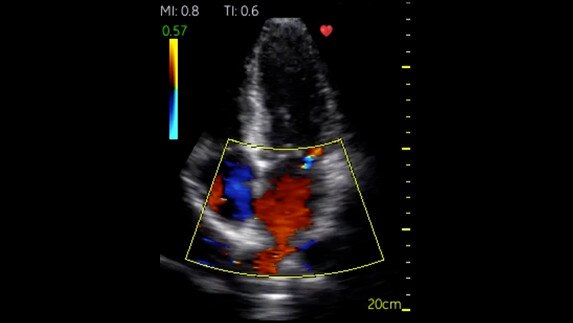

Phased Cardiac